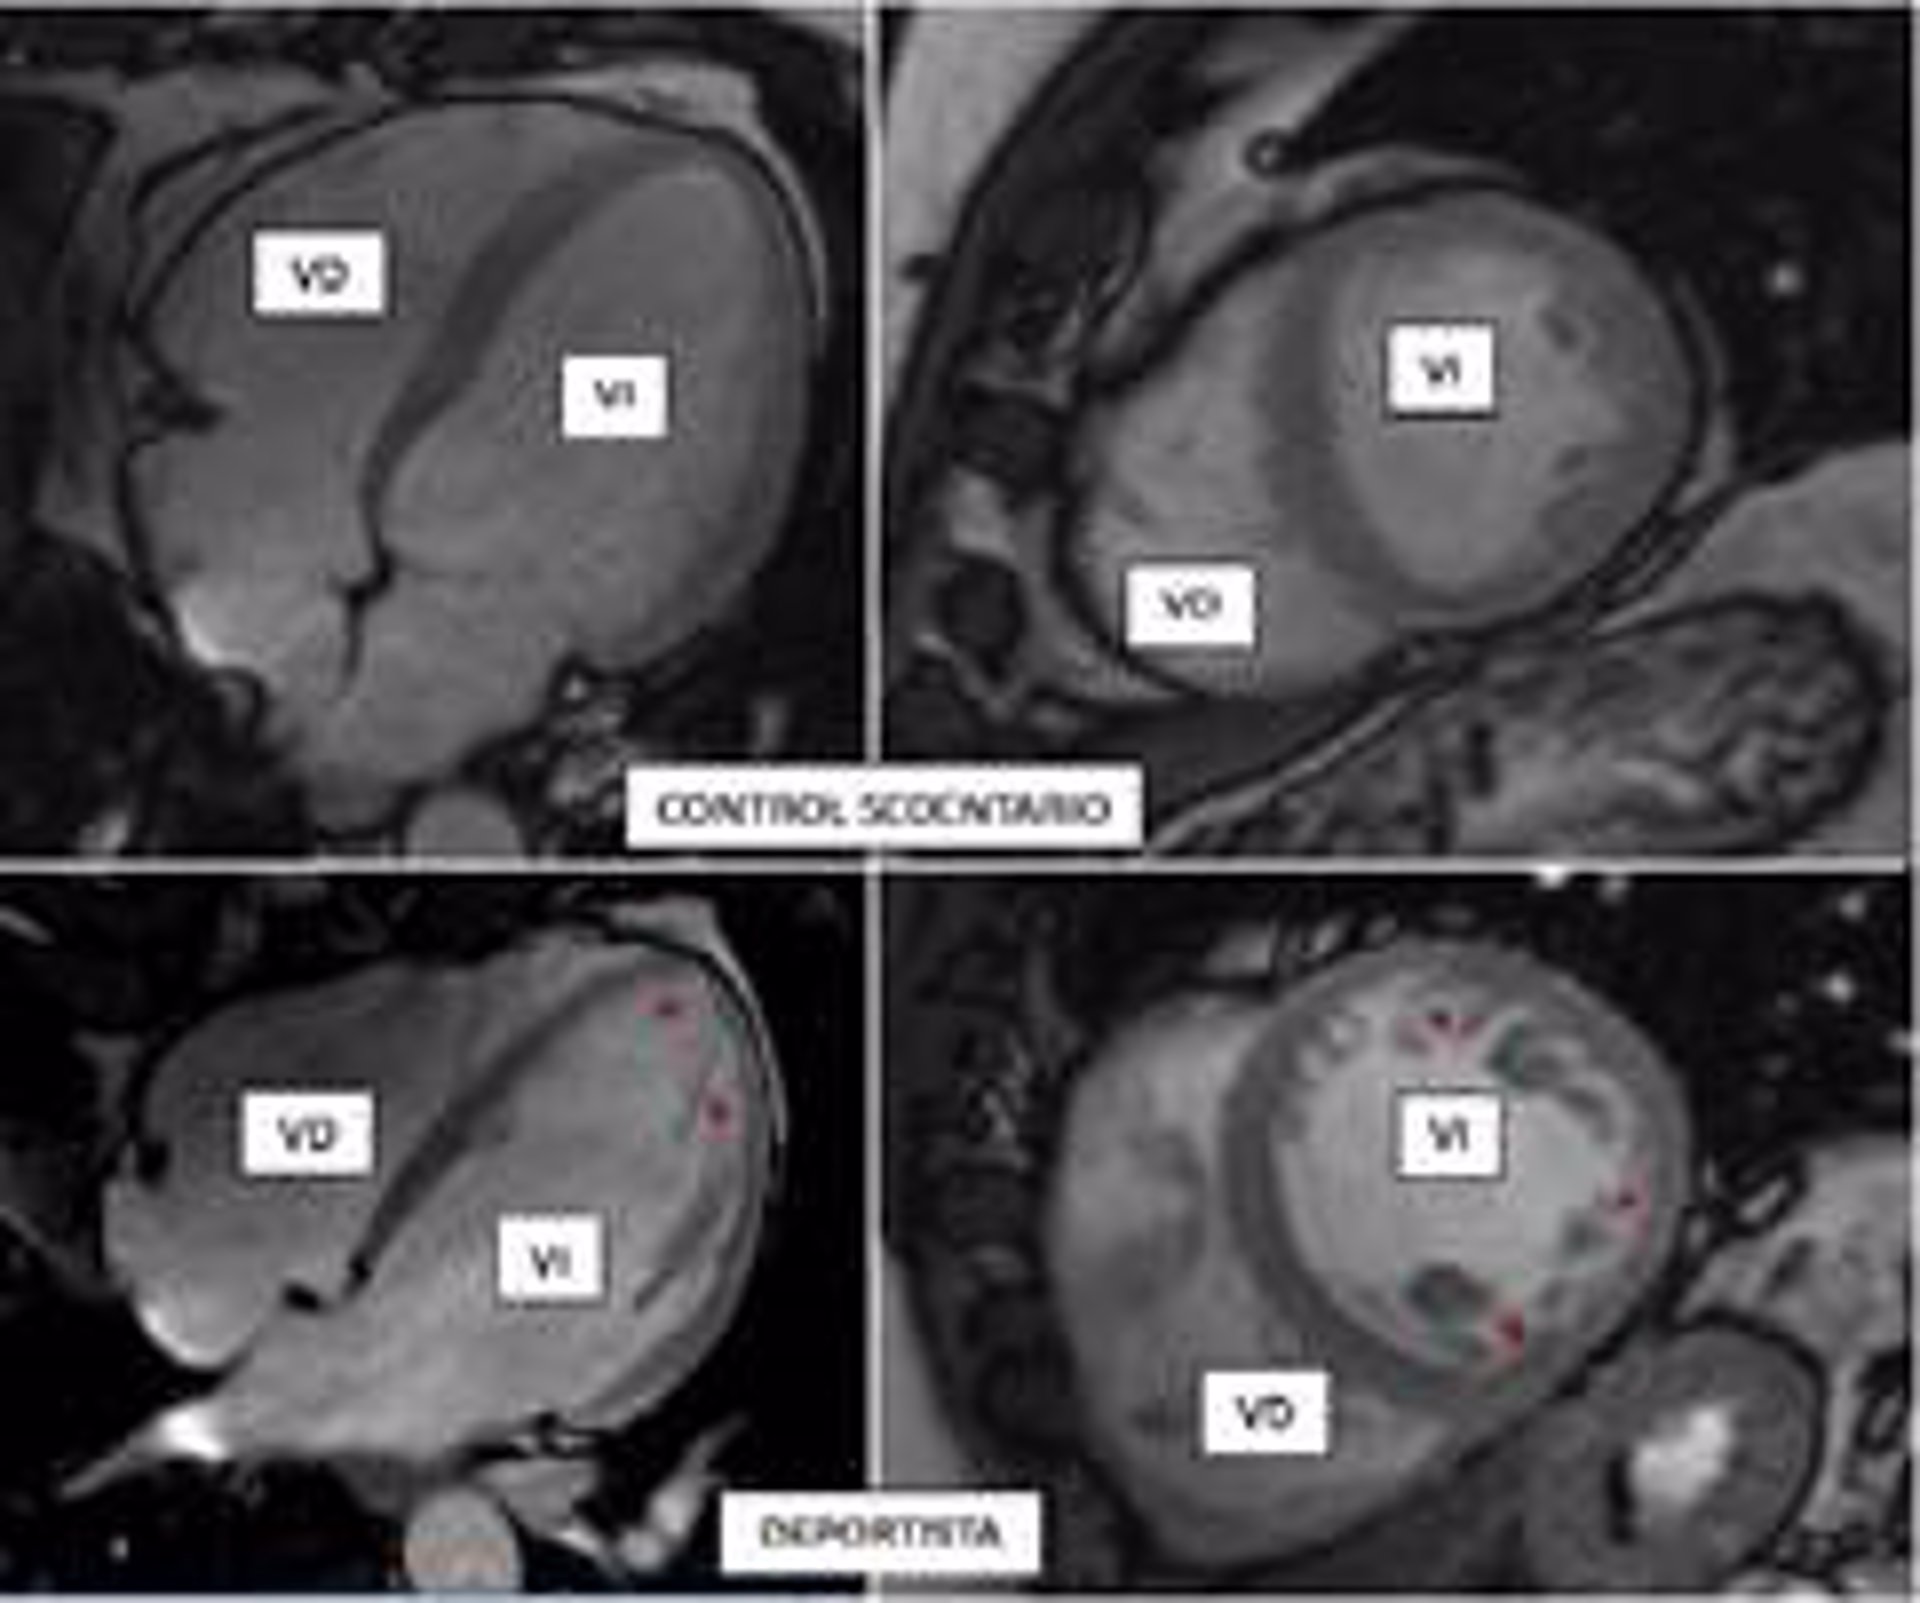

La práctica de ejercicio, intenso o moderado, es una de las recomendaciones de salud aceptadas por todos los expertos. Sin embargo, el entrenamiento de alta intensidad puede desencadenar una serie de cambios fisiológicos en el organismo, incluyendo el corazón. Por ejemplo, se sabe que los deportistas presentan una adaptación de su corazón al entrenamiento que, entre otros fenómenos, puede incluir un aumento de las trabéculas en su interior ("hipertrabeculación"), que es benigna pero que puede confundirse con una patología genética hereditaria, la miocardiopatía no compactada, que puede causar muerte súbita.

En la miocardiopatía no compactada, las paredes del corazón se adelgazan y el músculo cardiaco, habitualmente compacto, se sustituye por una porción esponjosa (trabeculada), que se comunica directamente con el interior de los ventrículos.

El trabajo ha evaluado mediante resonancia magnética cardiaca la presencia de criterios reconocidos de miocardiopatía no compactada en más de 700 participantes del estudio Pesa-CNIC-Santander, trabajadores sanos del Banco de Santander que realizan diferentes grados de actividad física, pero que no practican deporte de forma profesional.

Lo primero que se observó es que el músculo cardiaco de los participantes, que de forma persistente realizaron una actividad física vigorosa a lo largo de este periodo de tiempo, se adaptaba al ejercicio aumentando su volumen y su masa muscular. "Estos cambios son conocidos como corazón de atleta, y se consideran fisiológicos", explica García-Lunar.

Un hallazgo más novedoso fue que una tercera parte de los individuos (hombres y mujeres) con un nivel elevado de actividad física vigorosa habitual cumplía además los criterios diagnósticos de miocardiopatía no compactada, pero, obviamente, no estaban enfermos.